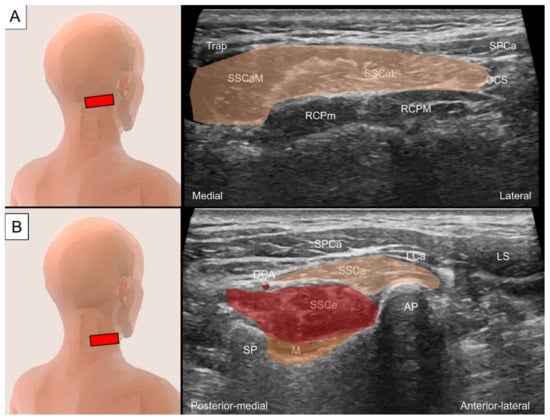

6.1. Sub-Occipital Muscles

6.1.1. Anatomy

6.1.2. Sonographic Scanning

6.1.3. Clinical Relevance